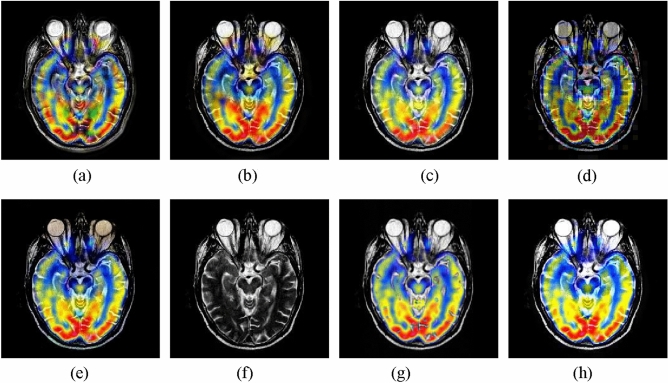

The second experiment is performed on the MRI and PET images. The fusion images yielded by different methods are shown in Fig. 4. In this example, the CNN-NSCT and NSST methods produce unsatisfactory performance caused by loss of energy. The NSST-ST method fails to preserve well the color information of the source PET image. The SR and GFF methods lead to severe color distortion. The resulting image of the DSWT-RBFN method cannot well retain the color information in the original PET image. In contrast, the proposed method can obtain higher visual effect in terms of both color preservation and detail extraction against other studied methods.

Figure 4.

Fusion results of different methods for MRI and PET images. (a) CNN-NSCT. (b) NSST. (c) NSST-ST. (d) SR. (e) MST-SR. (f) GFF. (g) DSWT-RBFN. (h) Our method.

The average objective indexes of different approaches on 11 pairs of MRI and PET images are presented in Table 2. We can see that the proposed method still produces the best performance against other compared methods, which also further verifies the advantage of the proposed method. For running time of all methods, it can be seen that the GFF method is efficient since it only requires image decomposition and fusion without involving any deep features. The computing time of the proposed method is moderate among all approaches.